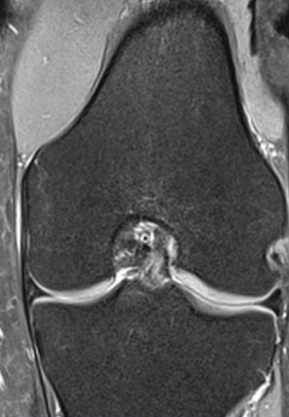

Możliwe do uzyskania obrazy diagnostyczne stawu kolanowego .

Obraz 3D z MRI

MRI